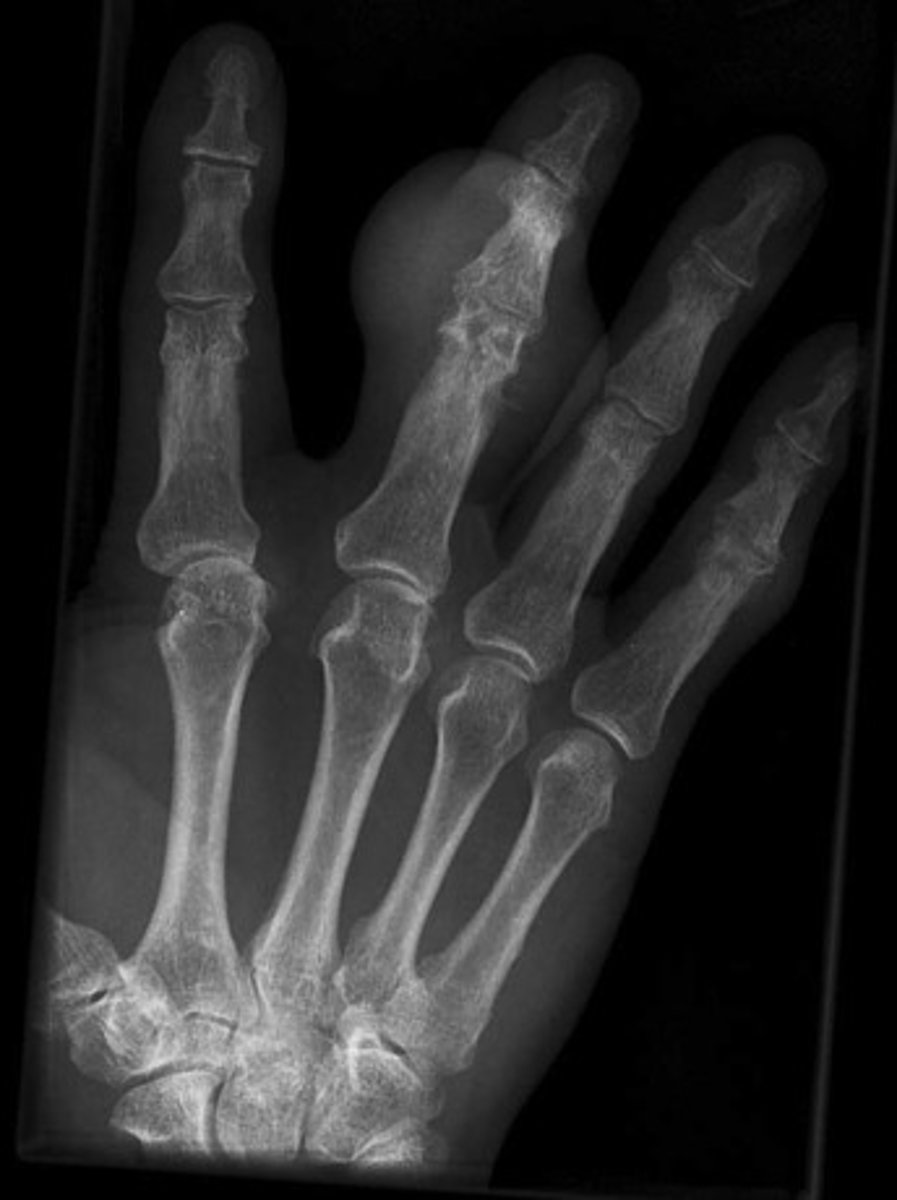

- 3rd digit

- Erosion with overhanging margin

- Dense soft tissue swelling

List findings

Gout

Diagnosis?

Refer to primary

Next step?